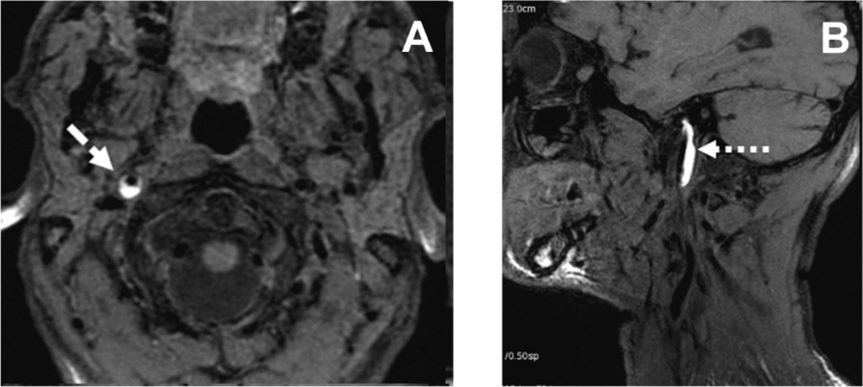

D’autres maladies artérielles ou du contenu sanguin peuvent être à l’origine d’un infarctus cérébral. Bien que rares, ces maladies sont cependant importantes à rechercher, car elles nécessitent parfois des traitements spécifiques. L’une d’entre elles – la dissection artérielle – mérite une mention particulière car elle représente la principale cause identifiable d’infarctus cérébral de l’adulte jeune. Elle est due à la formation d’un hématome dans la paroi artérielle, provoquant un rétrécissement voire une occlusion artérielle (Fig. 6).

Fig. 6 : Imagerie par résonance magnétique nucléaire (IRM) montant un hématome (en blanc) dans la paroi de

l’artère carotide interne. A: coupe transversale au niveau du cou. B. coupe sagittale au niveau du cou.